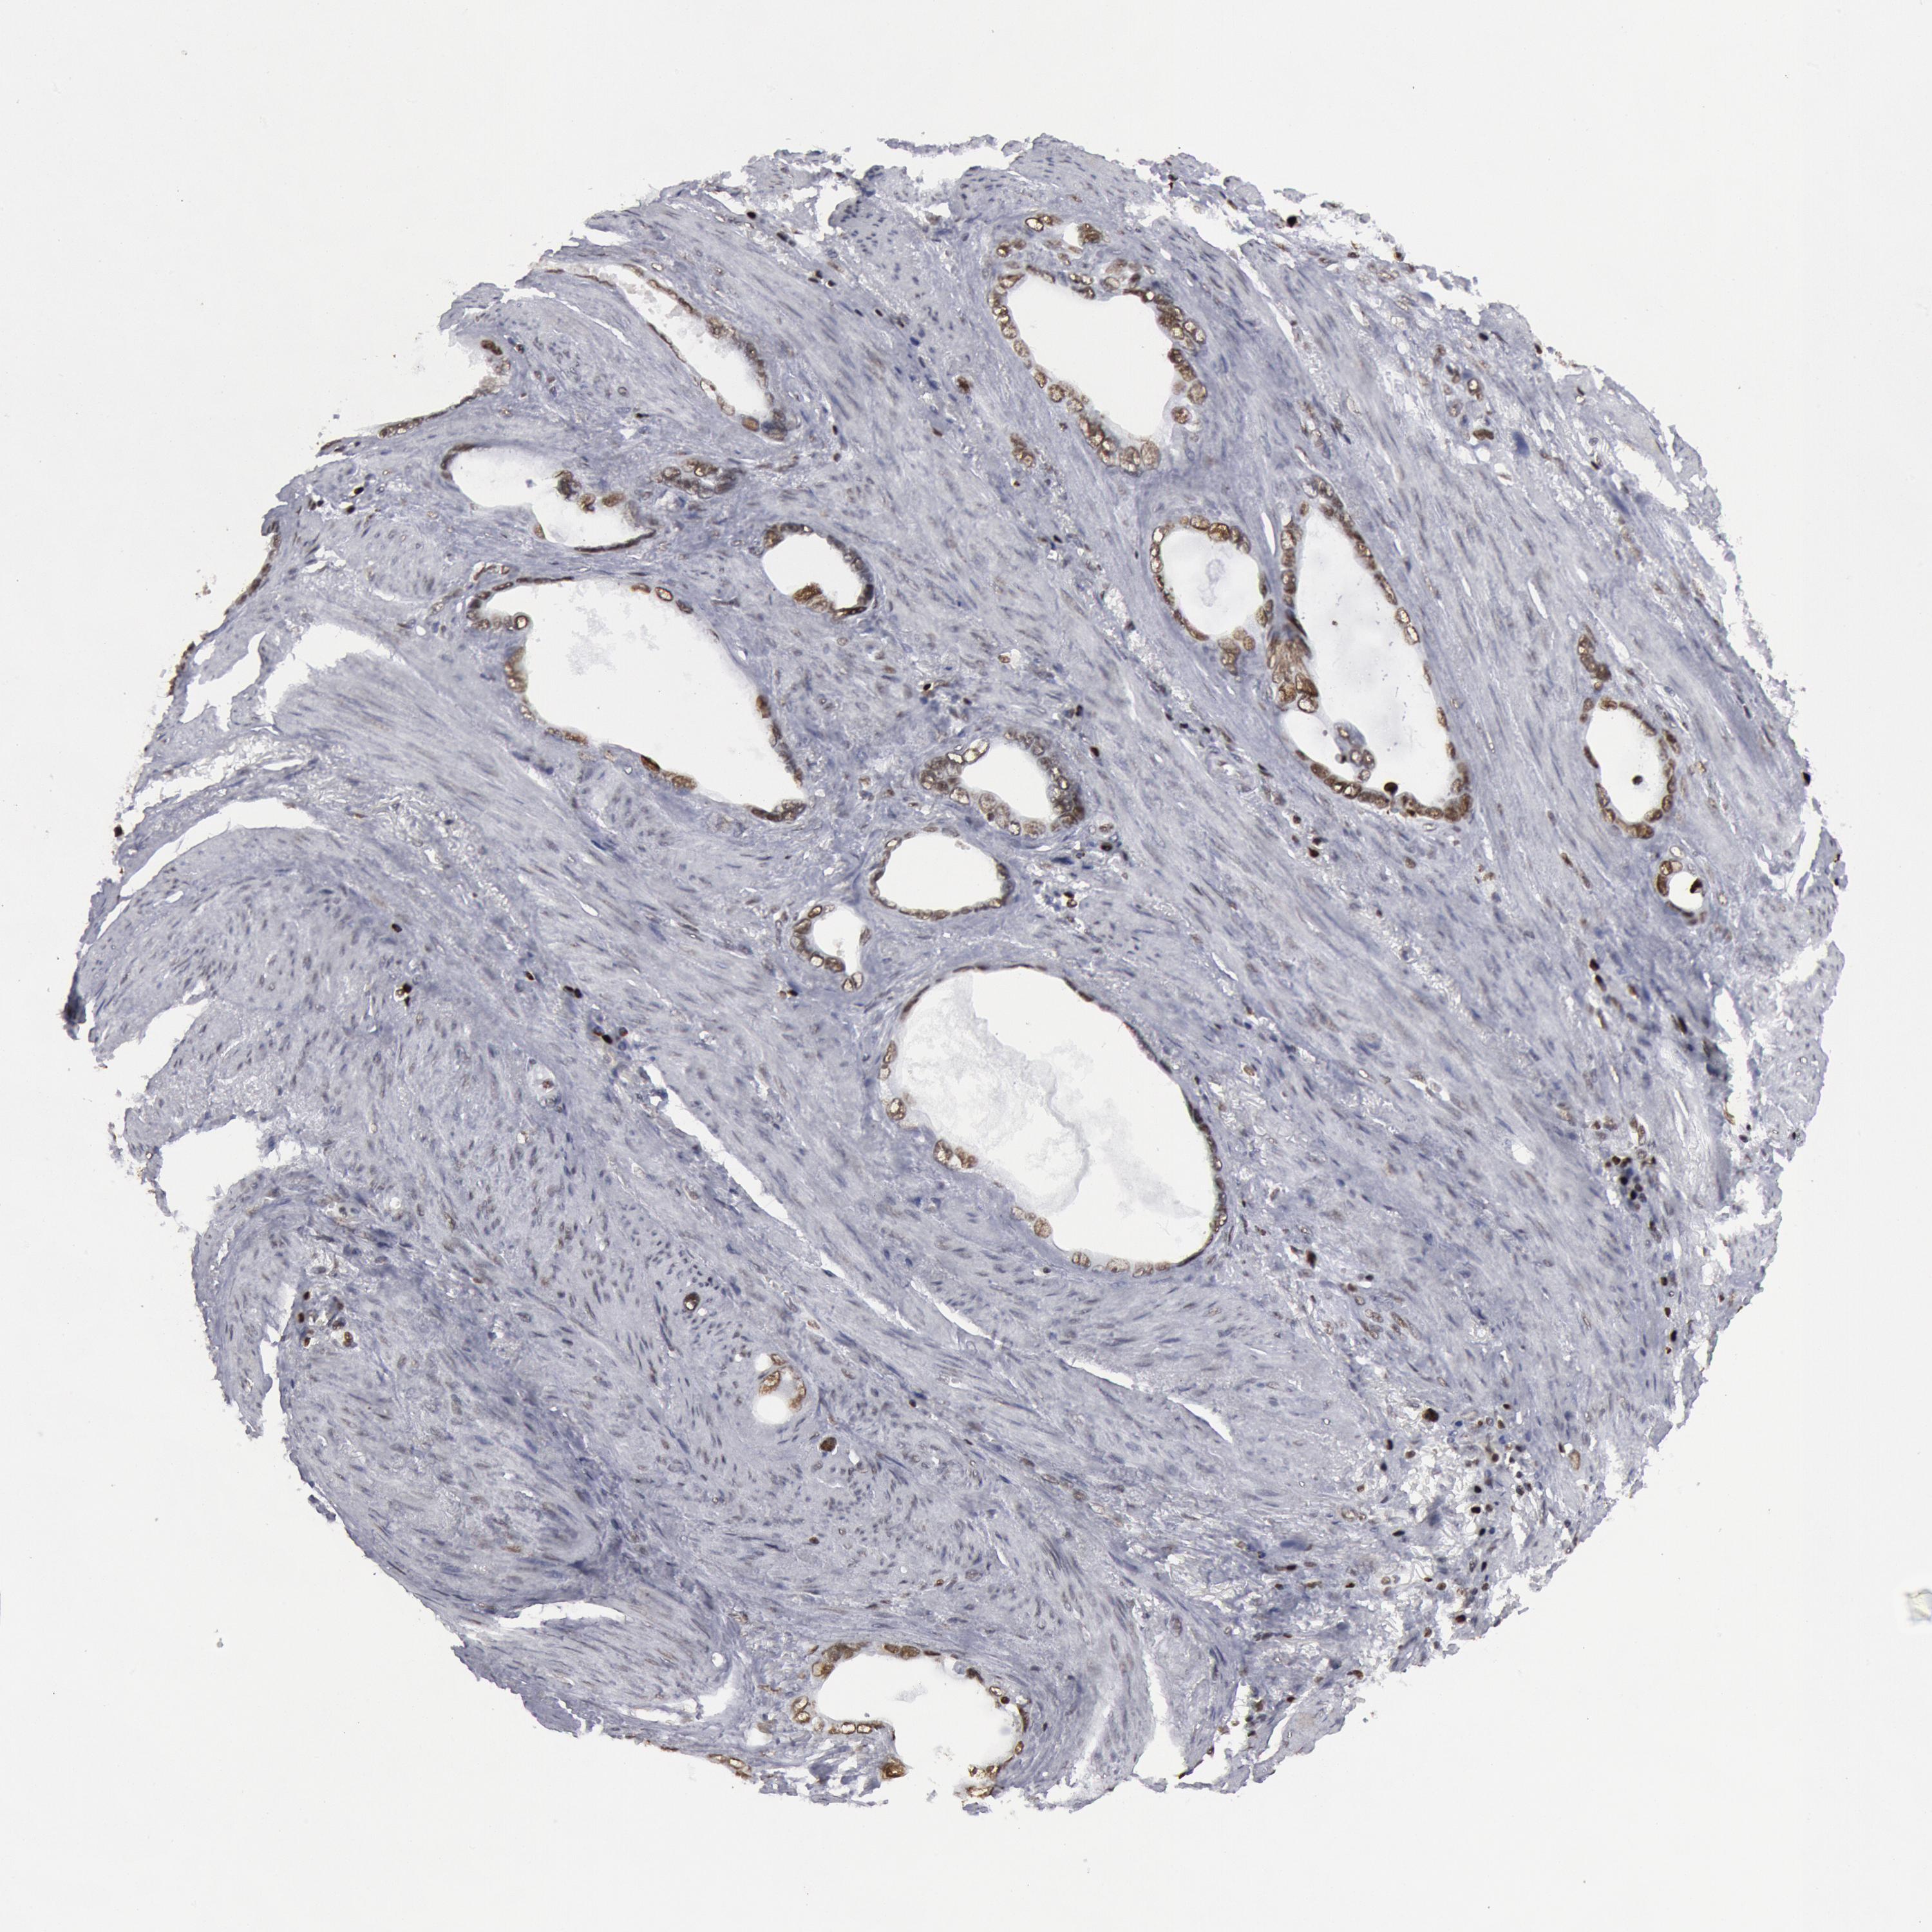

STOMACH CANCER - Protein expressioni

A mouse-over function shows sample information and annotation data. Click on an image to view it in a full screen mode. Samples can be filtered based on level of antibody staining by selecting one or several of the following categories: high, medium, low and not detected. The assay and annotation is described here.

Note that samples used for immunohistochemistry by the Human Protein Atlas do not correspond to samples in the TCGA dataset.

Antibody stainingi

Antibody staining in the annotated cell types in the current human tissue is reported as not detected, low, medium, or high, based on conventional immunohistochemistry profiling in selected tissues. This score is based on the combination of the staining intensity and fraction of stained cells.

Each image is clickable and will lead to virtual microscopy that enables deeper exploration of all samples and also displays staining intensity scores, fraction scores and subcellular localization as well as patient and tissue information for each sample.

Antibody HPA001311

Antibody CAB015351

Staining

High

Medium

Low

Not detected

Intensity

Strong

Moderate

Weak

Negative

Quantity

>75%

75%-25%

<25%

None

Location

Nuclear

Cytoplasmic/membranous

Cytoplasmic/membranous,nuclear

Adenocarcinoma, NOS